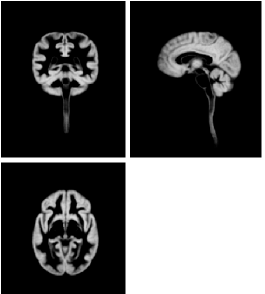

Refer to caption

(a) Gray matter

(b) White matter

Figure 3: Brain and spinal cord tissue probability maps of gray LABEL:sub@gray_tpm and white LABEL:sub@white_tpm matter, constructed as described in this paper.

Figure 3 illustrates orthogonal views of the gray and white matter tissue probability maps, where the gray matter map is obtained by evaluating the sum of the two top classes in Figure 2.